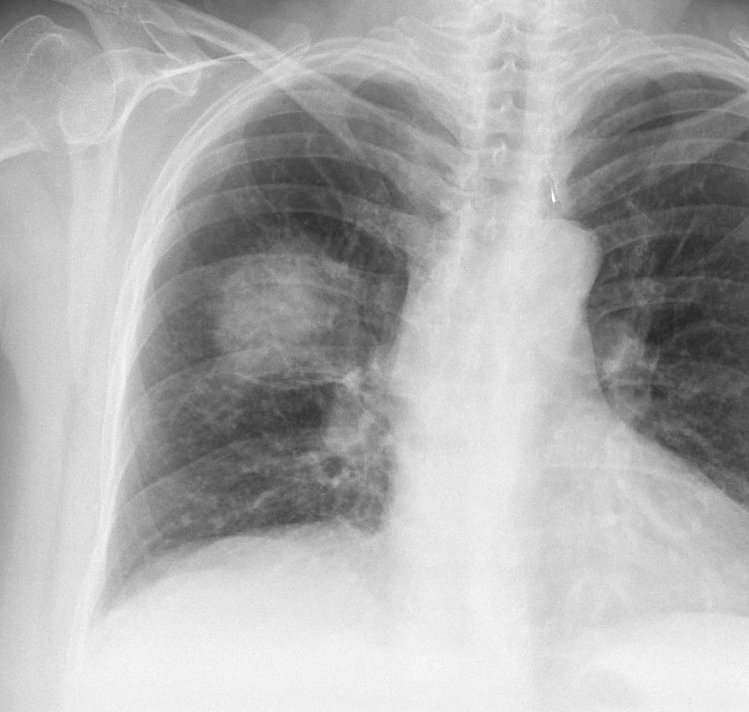

Gallery Pneumonia Case 1 Round pneumonia

Case 1 Round pneumonia